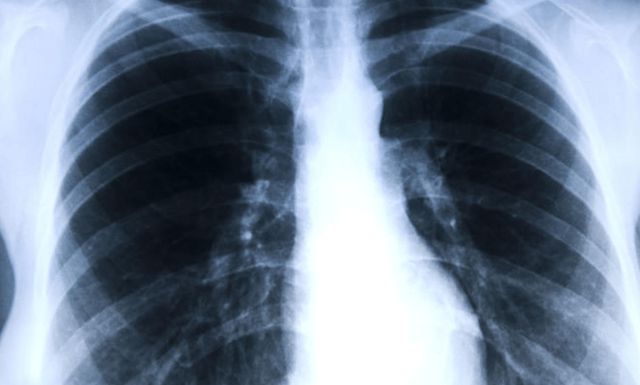

尤其是近年来随着CT的普及,越来越多的人被查出肺结节,养肺护肺成为了重中之重,那肺部出现结节时,身体都有哪些表现呢?这几个表现别忽视了: